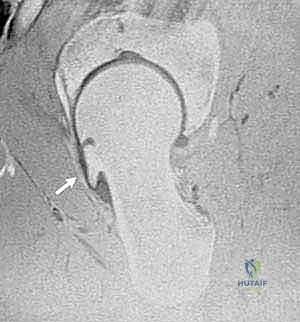

- الرنين المغناطيسي مع الصبغة (MRI Arthrogram): هو المعيار الذهبي لرؤية الأنسجة الرخوة. يتم حقن صبغة داخل المفصل لرؤية أدق تفاصيل تمزق الشفا الحقي وتآكل الغضروف.

6. إصلاح الشفا الحقي (Labral Repair):

إذا كان الشفا الحقي ممزقاً (وهو أمر شائع جداً)، لا يتم استئصاله، بل يتم إعادة تثبيته وخياطته بعناية فائقة باستخدام خطاطيف جراحية صغيرة (Suture Anchors) تزرع في العظم. الحفاظ على الشفا ضروري جداً للحفاظ على صحة المفصل على المدى الطويل.